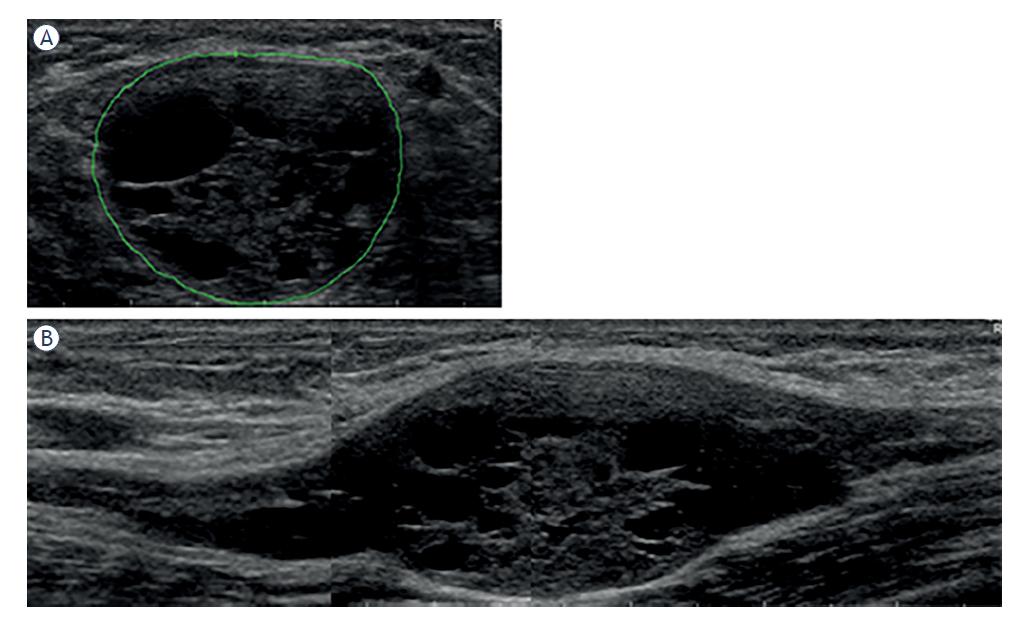

Of remaining 4 patients, 1 had definite and another probable tibial nerve schwannoma at the ankle, which is again a region of considerable mechanical stress. Another young woman had a fusiform thickening of the ulnar nerve in the forearm (patient #5, Figure 4). She had surgical release of the ulnar nerve exit from the flexor carpi ulnaris muscle, with no apparent benefit. She might also have perineurioma, or less likely neurofibroma. In the fourth man probable median nerve schwannoma in the forearm was a coincidental finding during US evaluation due to Lewis-Sumner syndrome, and caused no additional symptoms.

(A) Hands of a 26-year-old woman with 4-year history of muscle atrophy, weakness and numbness in the distal ulnar nerve territory (patient #5, Tables 2–3). Note intrinsic right palm muscle atrophy and clawing of the last two fingers. (B) On transverse ultrasonographic (US) view ulnar nerve cross sectional area (CSA) increased from 7 mm2 both proximally and distally to 20 mm2 in the middle of the lesion. (C) On longitudinal view a partially encapsulated, lobulated, fusiform hypoechoic right ulnar peripheral nerve tumour (PNT) of the forearm can be seen. Based on clinical and US features, we made a diagnosis of probable perineurioma.